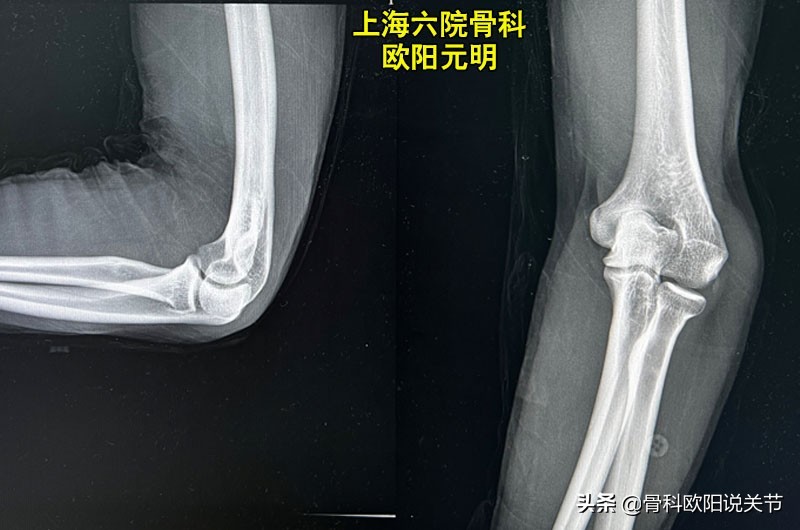

肘内翻主要是指肘关节伸拉内翻角度出现变形,可达15度到35度。前臂向身体内侧偏曲,X线光片提示肱骨和尺桡骨的对位关系发生了异常。